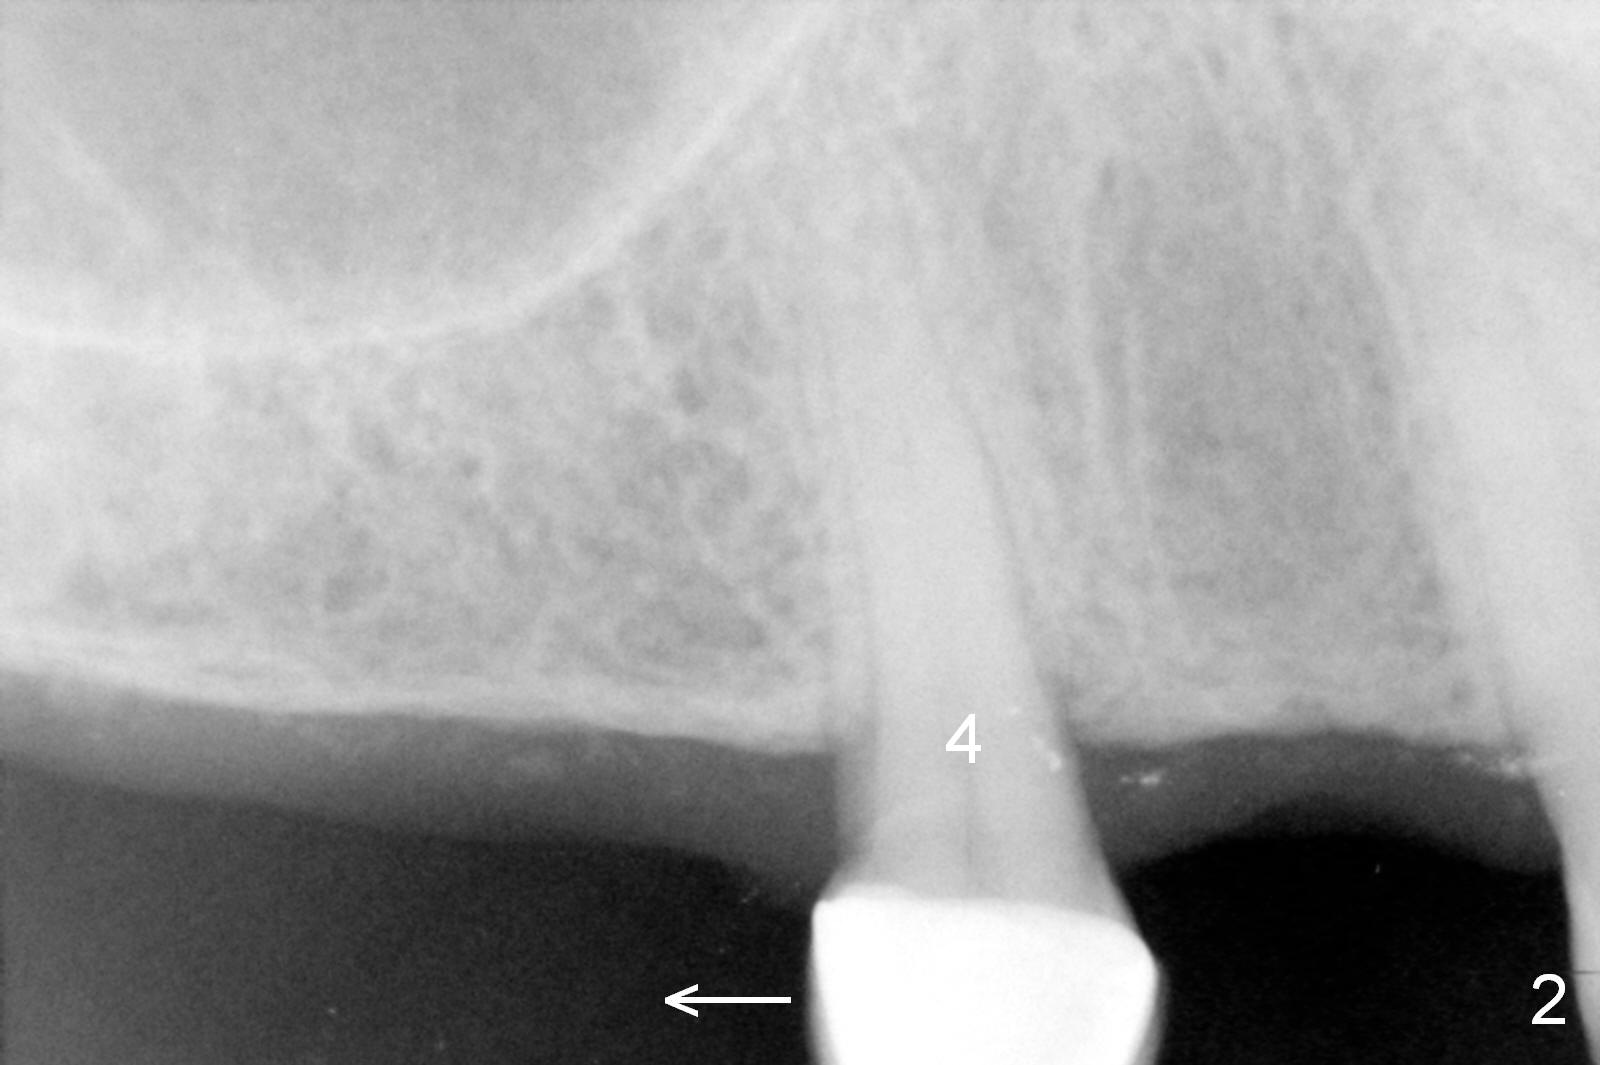

A 66-year-old man has lost several teeth (Fig.1,2). There is a particularly wide mesiodistal space for the site of #5 (Fig.1), probably due to distalization of the tooth #4 under heavy occlusion (Fig.2 arrow). A 4 mm tissue punch is used for access, followed by 1.6 mm pilot drill (Fig.3). After trajectory adjustment, a 2 mm parallel pin is inserted (Fig.4); later the osteotomy is moved distally (arrow). Finally a 4.5x14 mm implant is placed (Fig.5 I). Due to limited access, the implant is placed a little deeper than necessary; the gingival cuff of an abutment has to be longer (Fig.6 A: 5.8x4(3) mm). An immediate provisional is fabricated (Fig.7,8 P). The provisional looks wide (Fig.7). When the implant osteointegrates, limited orthodontic treatment will be done to idealize the space of #5 as follows.